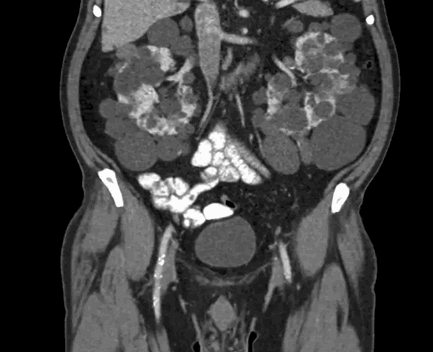

Компьютерная томография демонстрирует поликистоз почек и печени

Органы брюшной полости, ретроперитонеального пространства. КТ живота является точным методом для диагностики абдоминальных патологий:

опухолей (КТ показывает стадию и распространенность рака, ответ на лечение).